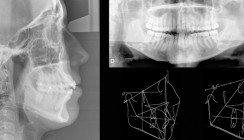

Fünf bis sieben Stunden kaute die Britin täglich Kaugummi. Von einem Tag auf den anderen änderte sich aber alles. Im einen Moment konnte sie noch lachen und kauen und im nächsten konnte sie den Mund nicht mehr öffnen. Starke Schmerzen und permanente Einschränkung beim Essen und Sprechen waren die Folge. Dabei hatte sie bereits seit zwei Jahren die Vorzeichen – ein gelegentliches Knacken im Kiefer beim Essen – nicht wahrgenommen. Die Muskulatur war überstrapaziert und die Gelenke abgenutzt. Nach dem Vorfall wurde sie physiotherapeutisch behandelt. In einer Operation entfernte man Reste des Abriebs aus dem Gewebe um die Kiefergelenke. Doch sie hat noch immer Schmerzen und kann den Mund nicht richtig öffnen. In einer weiteren Operation sollen Metallplatten an ihren Kiefergelenken eingesetzt werden, damit sie diese wieder normal bewegen kann.